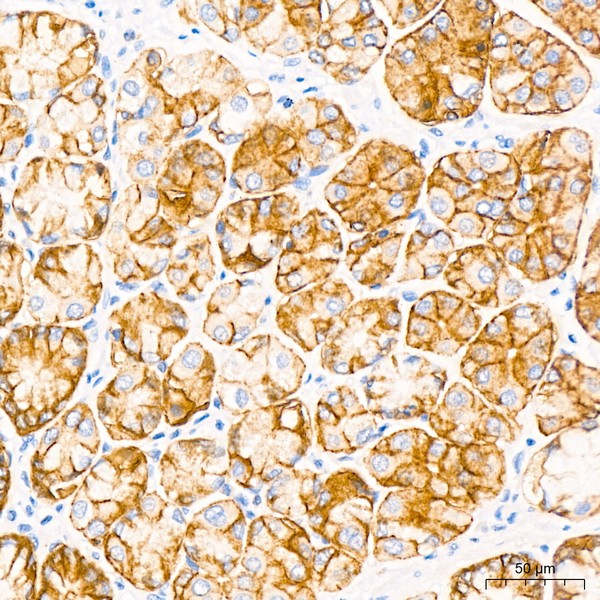

Images of Claudin18.2 Rabbit mAb (A20420)

Immunohistochemistry analysis of paraffin-embedded human stomach using CLDN18.2 Rabbit mAb (A20420) at dilution of 1:50 (40x lens).Perform high pressure antigen retrieval with 10 mM Tris/EDTA buffer pH 9.0 before commencing with IHC staining protocol.